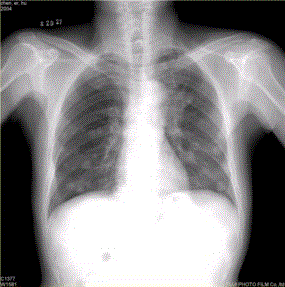

问题 患者男,45岁,因肝硬化、肝癌行肝移植术后6个月,咳嗽2周,来院复查。CR及CT影像如下图。 该例最可能的转移途径为

选项 A.经肺动脉 B.经肺动脉至淋巴管而后到肺外围 C.经纵隔淋巴结逆流到肺门淋巴结,再经肺内淋巴管到肺外周 D.经胸膜腔 E.经气道 F.经支气管动脉

答案 A